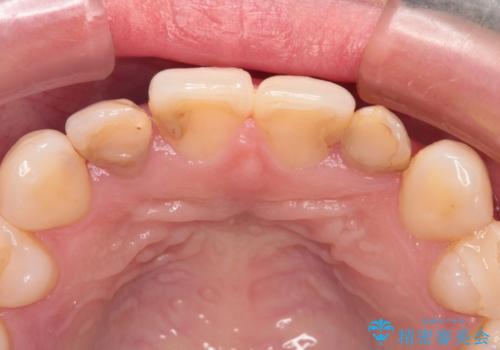

根管治療をしているため、歯の変色が認められます。

特に症状はなく、根管治療のやり直しは希望されなかったため、土台のやり替えから処置をしていくとととしました。